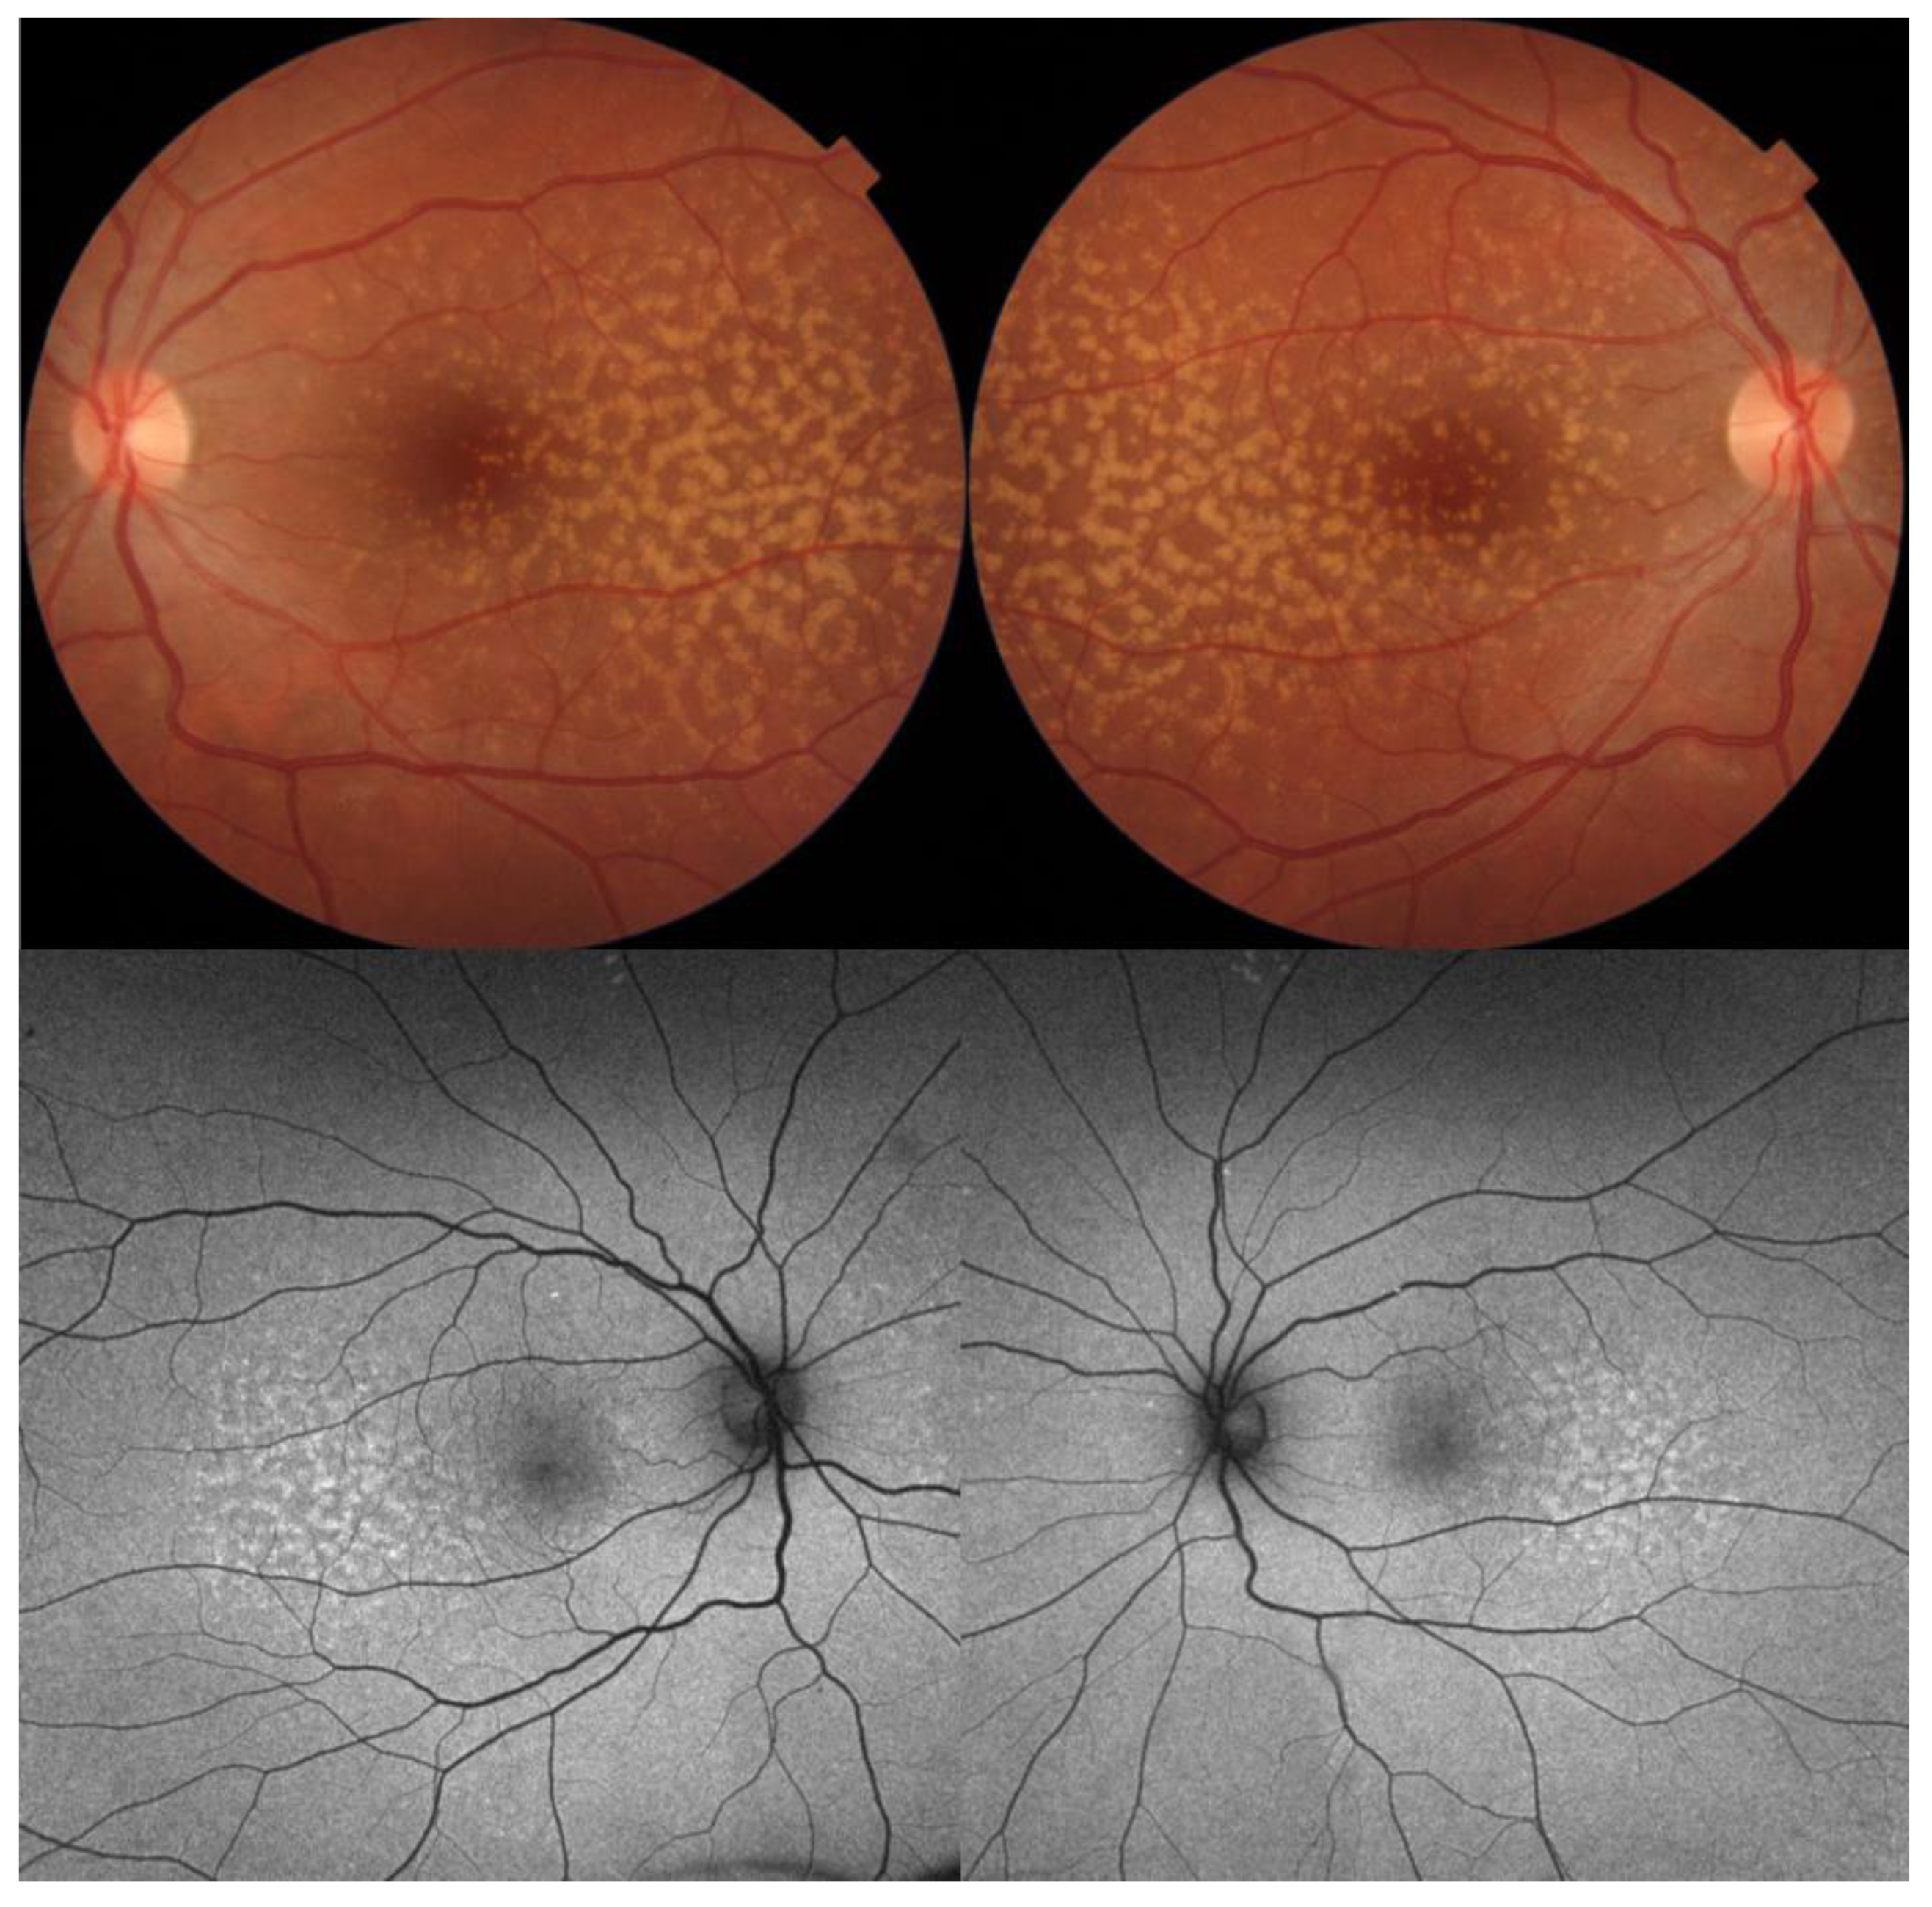

6. Autosomal Dominant Drusen

| Autosomal dominant drusen |

|